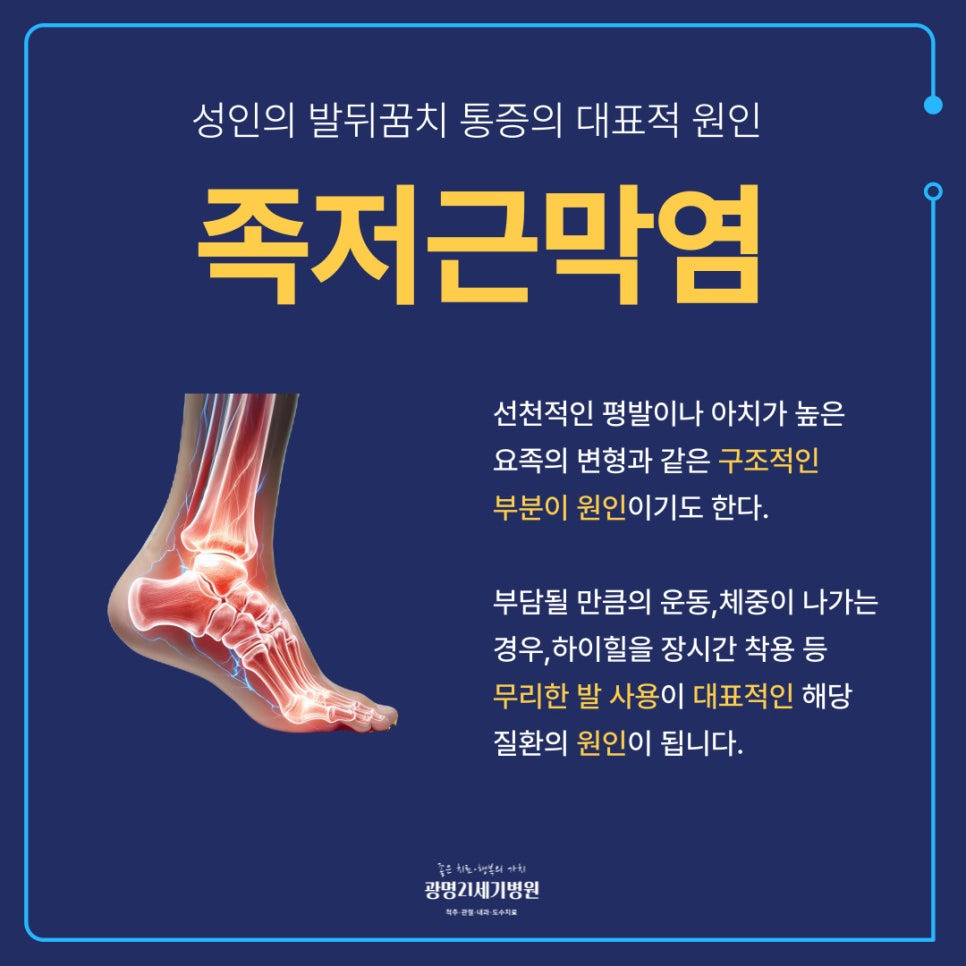

족저근막염은 선천적인 평발이나 아치가 높은 요족 변형과 같은 구조적인 부분에 의해 발생하게 돼요. 또한 발바닥에 충격이나 피로가 생기는 행동이나 습관이 큰 영향을 미치는데요. 족저근막염이 발생하는 원인은 다음과 같아요.

- 하이힐 등의 밑창이 딱딱한 신발을 착용

- 발바닥의 지속적인 충격을 주는 활동 및 운동

- 과체중

- 평발 및 요족 변형

위와 같은 원인에 의해 발생하는 족저근막염은 족저근막에 반복적으로 미세한 손상을 입어 염증이 발생하면서 나타나게 되는데요.